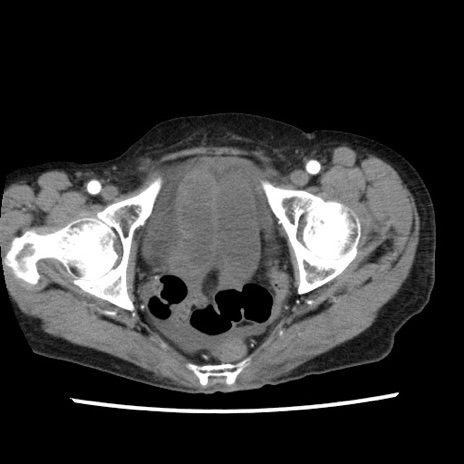

【症例】80歳代女性

【主訴】腹痛

【現病歴】8時間前から腹痛あり来院。

【既往歴】糖尿病、脂質異常症、子宮体癌にて子宮全摘術

【身体所見】意識清明・会話良好だが腹痛で苦悶様、全腹部にわたって反跳痛と圧痛あり

【データ】WBC 13600、CRP 0.14、LDH 224、CK 90